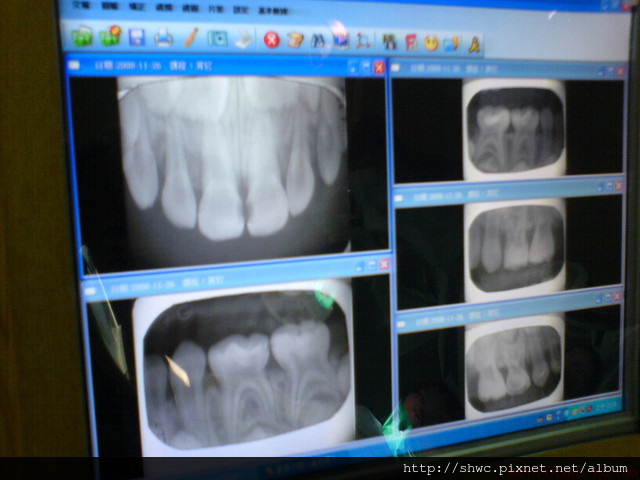

輪到小夏了!牙醫師先幫他檢查牙齒,結果發現好幾顆蛀牙,因此就拍了好幾張牙齒的X光照片。

醫師說X光顯示有好幾顆已經蛀到神經的位置,恐怕要抽神經。

不然等到以後牙痛或腫的時候,恐怕也要抽神經甚至整顆牙拔除。